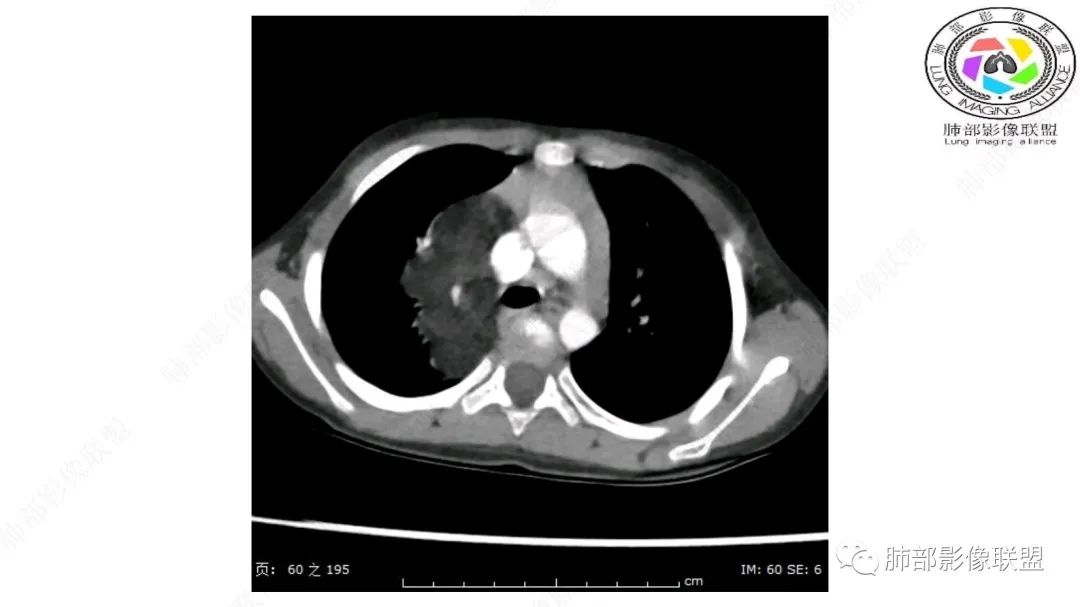

右上纵隔混杂密度肿块,边缘光整,与纵隔分界清,其内多发脂肪密度,增强无明显强化,其内血管穿行,考虑纵隔脂肪母细胞瘤,鉴别畸胎瘤,脂肪肉瘤。

右纵隔团状,密度不均,脂肪密度为主,内可见腺体样组织,类似乳腺,病灶边缘有分叶,与胸腺关系密切,增强后血管穿行。考虑胸腺脂肪瘤(不典型垂乳征),鉴别畸胎瘤。

三岁小儿,右侧纵隔巨大脂肪密度肿块,肺动脉穿行其中,密度欠均匀,未见明确实性成分,纵隔脂肪母细胞瘤,冬眠瘤鉴别纵隔脂肪增多症(多弥漫对称)。

患儿3岁 咳嗽检查发现纵隔占位。右肺上叶受压表现,占位以脂肪组织密度为主,似见分隔,首先考虑为脂肪母细胞瘤,鉴别脂肪瘤,畸胎瘤。

幼儿,右上纵隔团块状脂肪密度影,边缘清晰,内可见血管及支气管穿行,考虑脂肪瘤,鉴别畸胎瘤。

幼儿,右上纵膈团块,脂肪密度,内见分隔,增强病灶内见血管穿行,结合患者年龄,考虑脂肪母细胞瘤,鉴别脂肪瘤。

纵隔畸胎瘤,右前上纵隔团状脂肪密度?粘液样密度为主病变,病灶软边缘有分叶,内可见分隔,增强后血管穿行。3岁。考虑纵隔脂肪母细胞瘤,鉴别畸胎瘤。

病灶属于交界区,主体位于肺内,占位效应明显,前方突入胸壁,胸腺受压变形,胸膜显示欠清楚;病灶包绕上叶肺动脉;似乎有体动脉供血。符合肺内的点:包绕上叶肺动脉分支;符合纵隔的点:前方似乎突入胸壁,与胸腺关系比较密切,但是与上腔静脉的关系提示病灶不支持纵隔来源,前纵隔的常规会将上腔静脉受压后移、外移,这是不符合的。

手术记录:见右肺上叶肿物,肿物与右肺上叶关系密切。与纵隔无粘连,逐步分离肿物,见肿物大小约6cm*5cm,边界清楚,于右肺上叶粘连,边界清楚,肿物包绕右肺上叶血管及支气管。超声刀逐步游离肿物,完整切除肿物,右肺上叶肺组织无破溃,表面无出血。

1.右上肺-纵隔交界区巨块影,主体位于右肺一侧,紧贴胸腺、头臂干、右锁骨下动脉、上腔静脉、奇静脉等,不能分离,但病灶整体边界清楚。注意上述相邻腔静脉等结构未见受压变形,纵隔亦未见明显向左推移,至少提示两点:

2.肺动脉穿行也许是肺内来源最重要支持点!